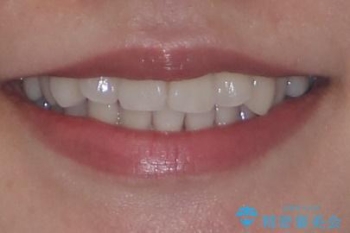

- 「歯並び全体のデコボコが気になる」「上下の歯の正中(中心)がずれているのが気になる」

このようなお悩みを主訴にご来院された患者様の矯正治療症例をご紹介します。

初診時、上下顎ともに歯列の不正が認められ、特に左下の小臼歯が大きく歯列から外れている状態でした。その影響により、下顎の正中が左側へシフトしており、見た目だけでなく噛み合わせにも影響が出ていました。